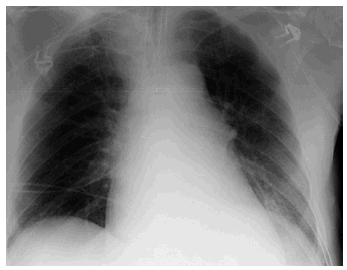

Paciente de 72 años de edad ingresado en Unidad de Cuidados Intensivos (UCI) con insuficiencia respiratoria global por una reagudización de enfermedad pulmonar obstructiva (EPOC). El paciente tiene dificultades para la desconexión de la ventilación mecánica por atelectasias de repetición y acidosis respiratoria grave. En la figura 1 se observa la radiografía de tórax en ventilación mecánica y en la figura 2 una de la imágenes de atelectasia al reducir el soporte ventilatorio. Se realizó electromiograma de diafragma mediante punción del pilar anterior por acceso retroesternal, en el que aparecieron datos de denervación (fibrilaciones y ondas rítmicas de denervación "marcadas con un circulo rojo") (fig. 3). El paciente fue dado de alta de UCI y del hospital con soporte ventilatorio parcial.

Figura 3.